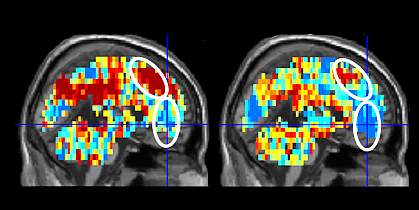

The scientists used data from 33 participants to train a machine-learning system to spot differences in networks of brain activity. They then tested it on brain images from 34 participants. The system correctly identified 15 of 17 suicidal people and 16 of 17 controls—an accuracy of 91%. The strongest differences between the groups, in order, were for the words “death”, “carefree,” “good,” “cruelty,” “praise,” and “trouble.” Within the group of 17 people with suicidal thoughts, the system was also able to distinguish the 9 who had previously made a suicide attempt from the 8 who hadn’t with an accuracy of 94% (16 out of 17). Discriminating regions were spread across several areas of the brain.

Previous studies have identified signatures of brain activity with different emotions. The researchers found that the neural signatures of the emotions sadness, shame, anger, and pride differed between people with suicidal thoughts and healthy controls for the six discriminating words. Among the 34 participants, a machine-learning system could distinguish between the groups based on emotional signatures with an accuracy of 85%.